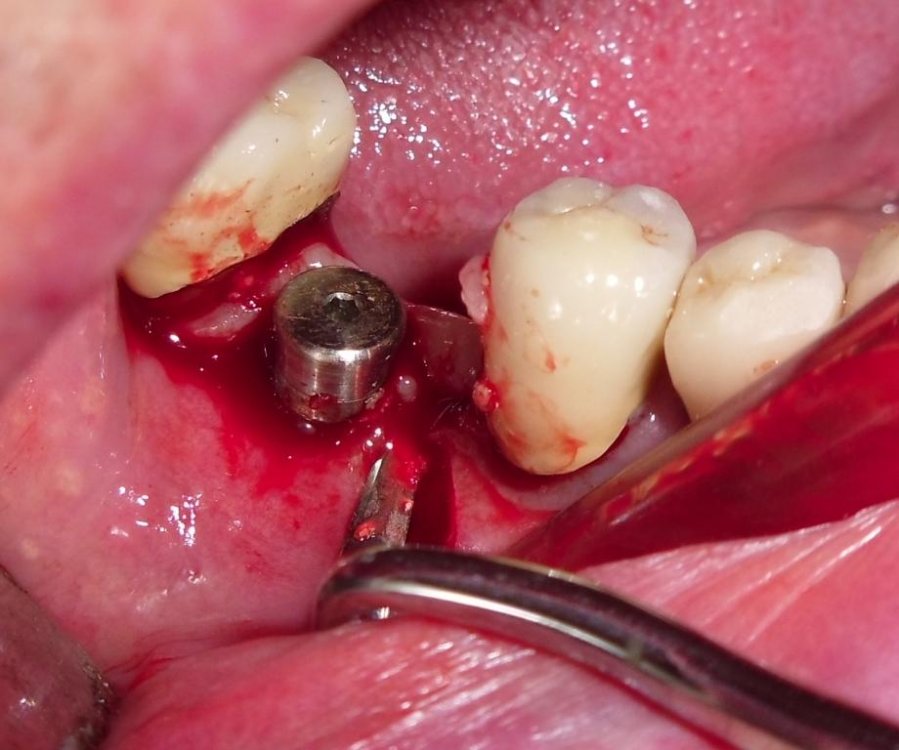

Debridement del difetto mediante strumenti manuali e ultrasonici con inserti dedicati e decontaminazione della superficie implantare  mediante applicazione topica di Ambramicina

Implantoplastica e rimodelllamento della cresta ossea

Posizionamento apicale del lembo suturato con poliestere 5-0